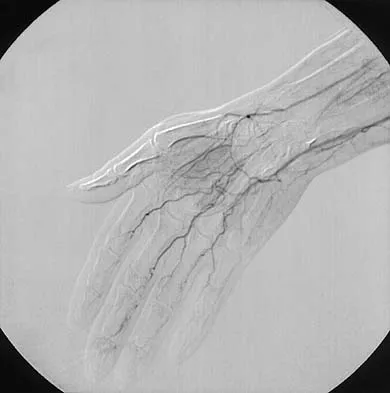

An infant is born with a mass that involves both the volar and dorsal compartments of the left arm. A clinical photograph and biopsy specimen are shown in Figures 41a and 41b. What is the best initial course of action?

Explanation